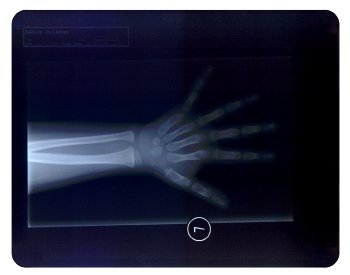

X Işınları ile film emülsiyonunun tepkimesi sonucu, ışığın şiddetine ve pozlama süresine göre bir cismin içini görmek, röntgen filmleriyle mümkün olmaktadır.